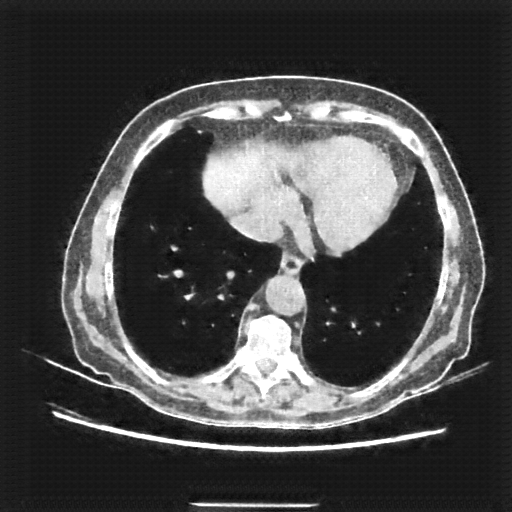

Original VENOUS CT scan

Lung window (WL -600, WW 1500 β†’ Low βˆ’1350, High +150)

Generated VENOUS CT scan (A→B translation)